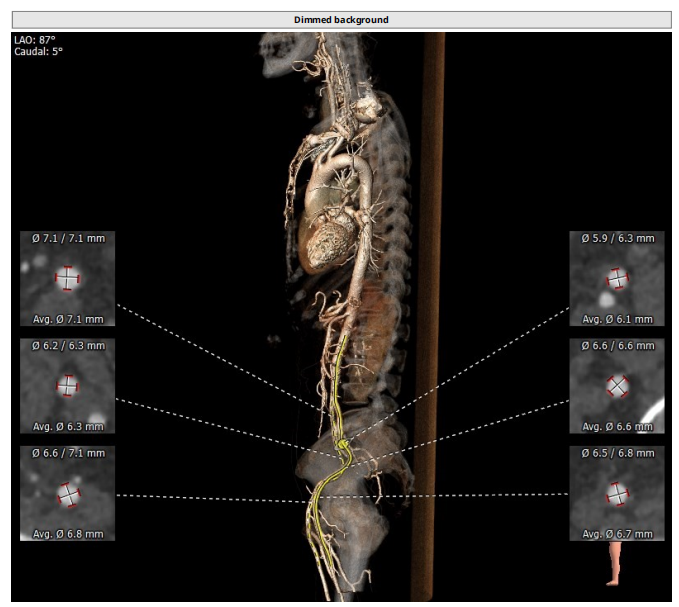

术前CT评估

整体情况

瓣环:16.9mm,左室流出道:16.7mm

STJ:23.9mm,升主动脉:31.4mm

瓣叶增厚 右冠高度:10.9mm,左冠高度:9.5mm

心室大小可

工作体位:LAO:12°CRA:5°,左冠切线位:LAO:26° CRA:19°

右股为主入路